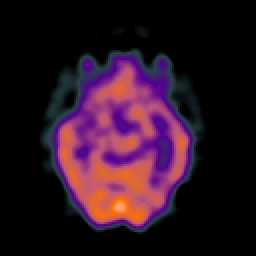

SPECT TC Study #4 -- Slice #23

[Home][Help][Clinical][Tour 1][Tour 2][Tour 3] Slice 23